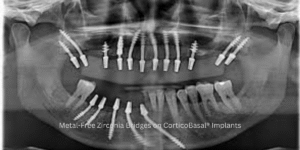

Modern dentistry is evolving rapidly, and CorticoBasal® Implants stand at the forefront of this transformation. Unlike traditional systems that depend on

Traditional dental implants often come with a long list of prerequisites — including bone grafting, sinus lifting, or lengthy healing periods.

Dental implants have transformed modern dentistry by providing patients with a permanent and functional replacement for missing teeth. However, not all